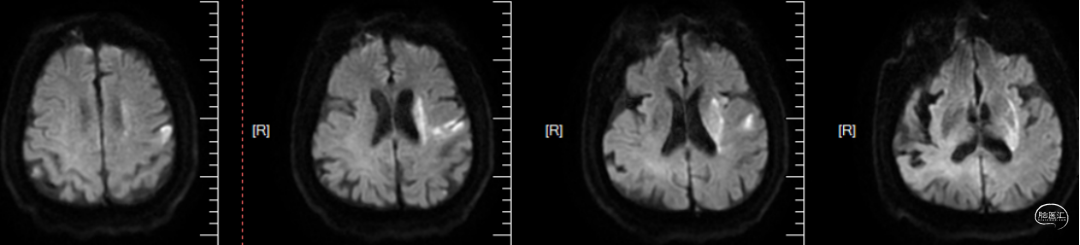

入院后头颅MRI评估提示:左侧额顶叶及侧脑室旁近期梗塞,见下图1。

图1.头颅DWI检查